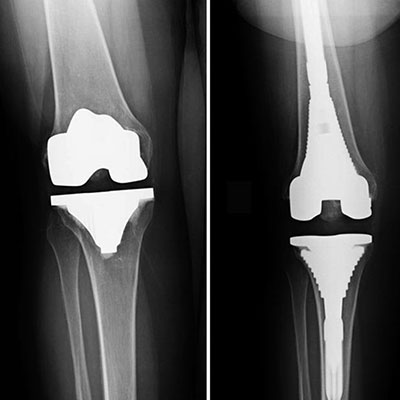

Knee replacement surgery involves removing damaged portions of the knee joint and replacing them with artificial components made of metal, ceramic or plastic. The procedure is usually recommended for individuals with severe arthritis, injury or other conditions that limit their ability to perform daily activities.

Knee replacement surgery typically lasts one to two hours and is performed under general or regional anesthesia. The surgeon makes an incision above the knee to access the joint, removes the damaged portions and implants the prosthetic components. The incision is then closed and the knee is bandaged.